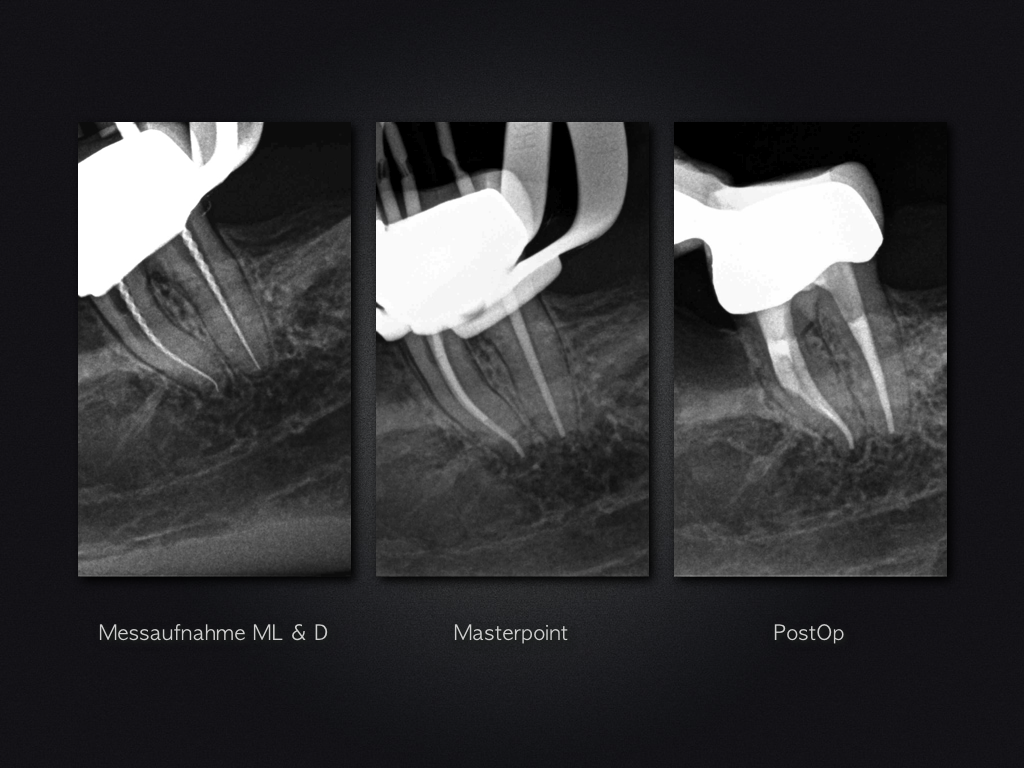

Glück gehabt